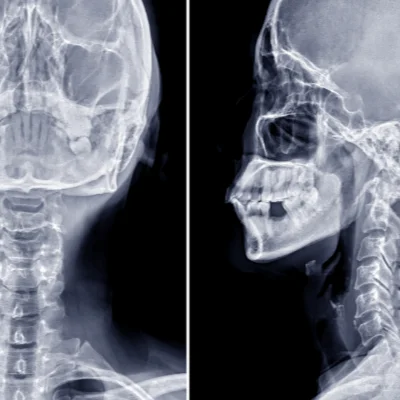

Skull and Sinus X-Ray

For trauma, sinusitis, or structural abnormalities.